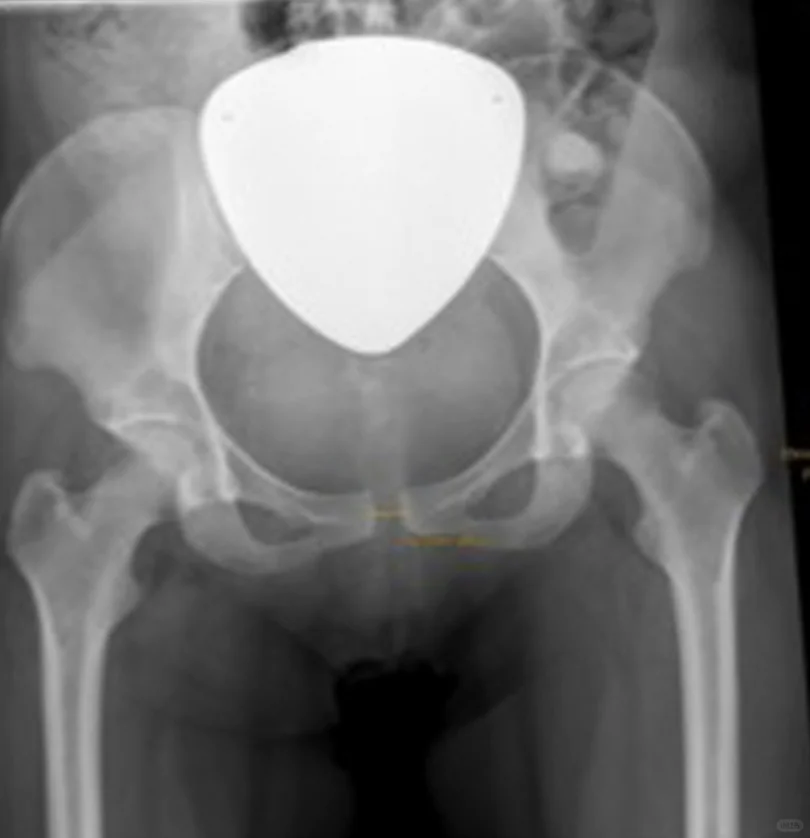

[樱花R]没有怀孕时正常耻骨联合间隙为4-5mm;而孕妇的耻骨间隙可增加至少2-3mm。

影像学检查发现分离超过10-13mm,可诊断耻骨联合分离。